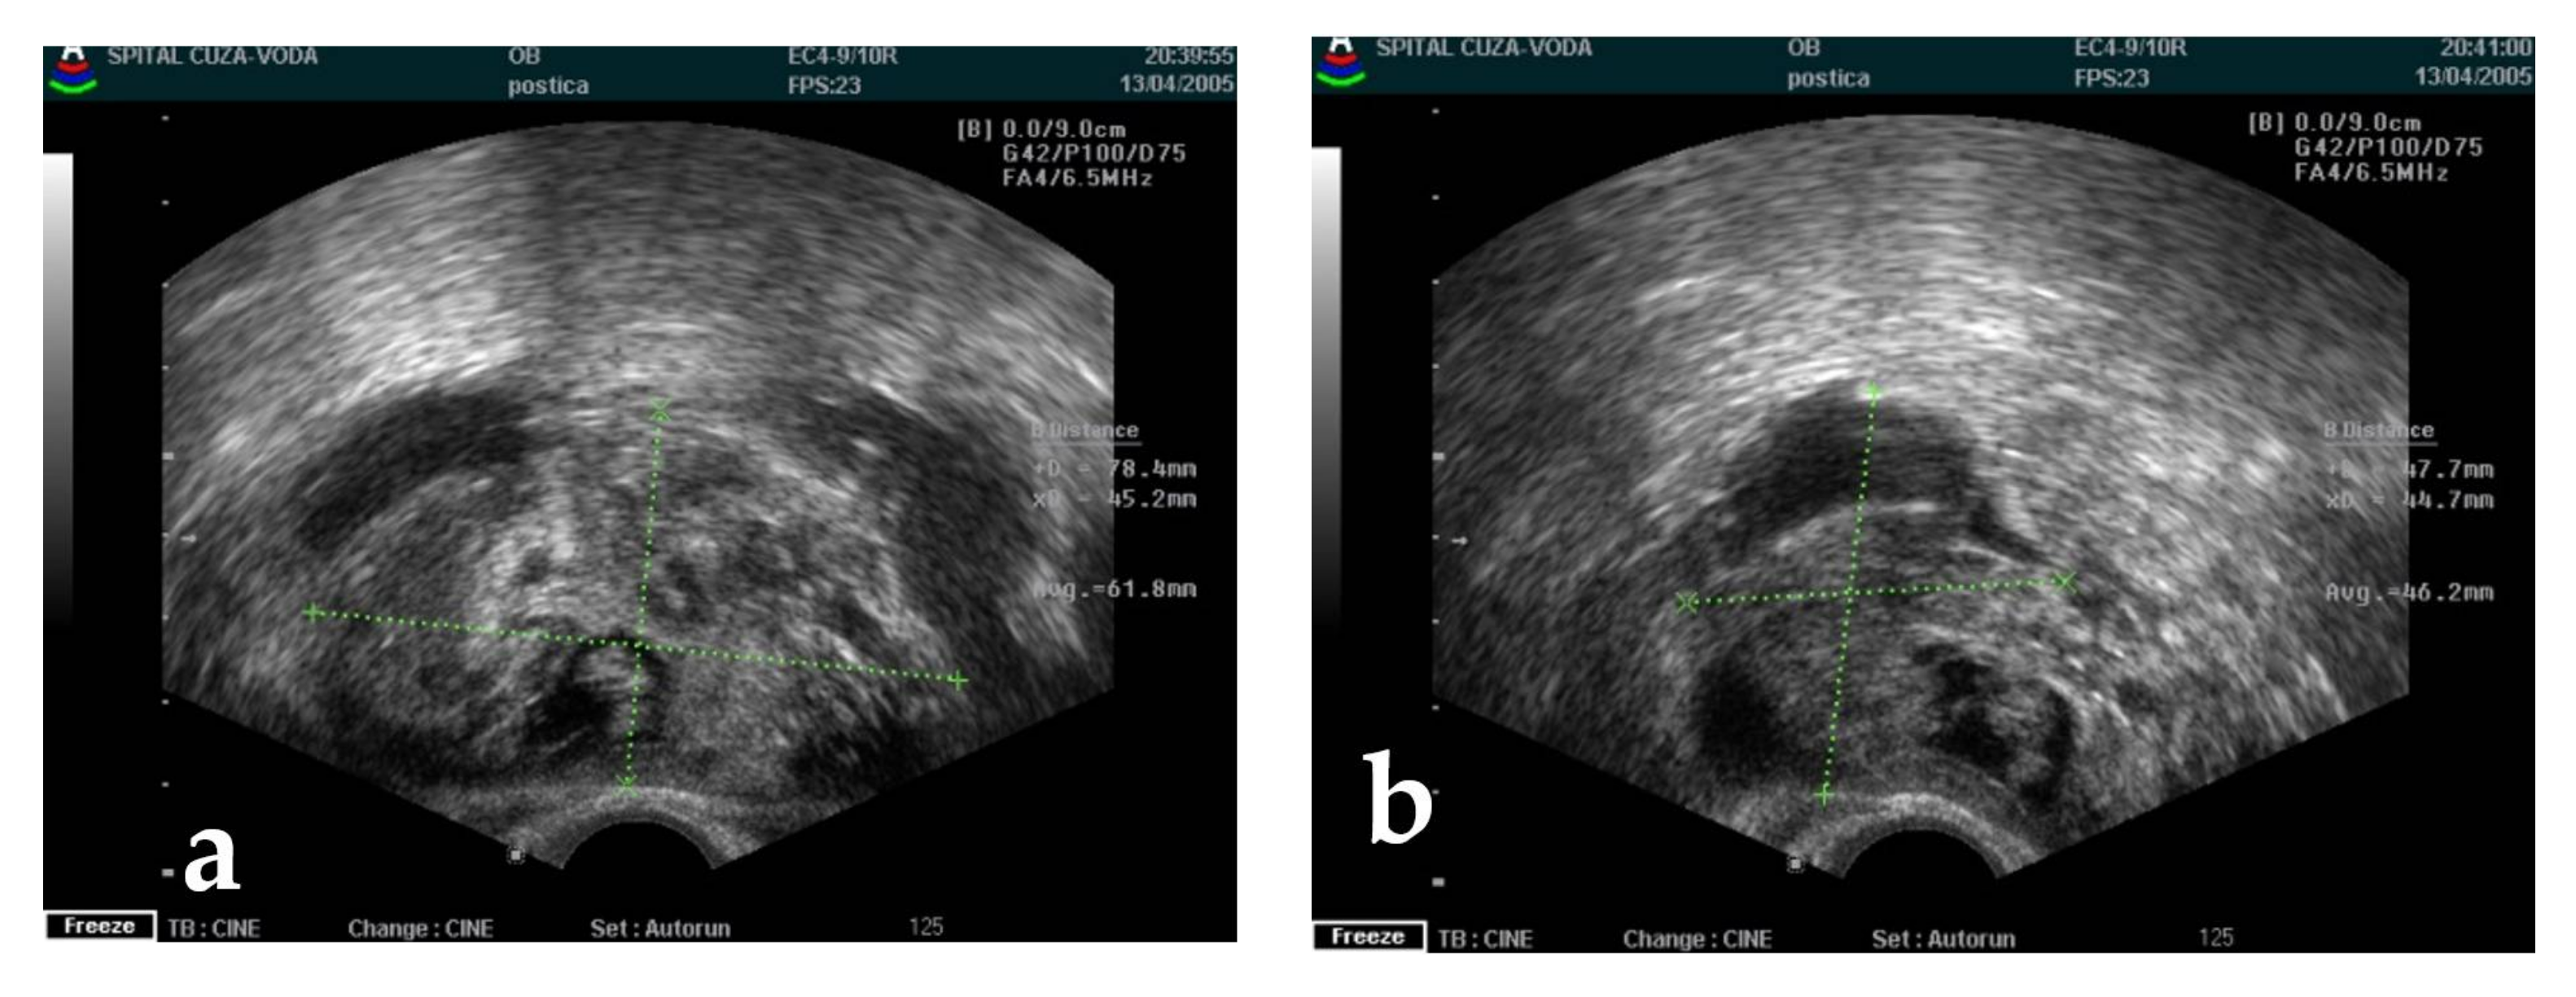

| 6 | 51 | right | 10 | 2005 | Serous cystadenoma Ascites | 45 |